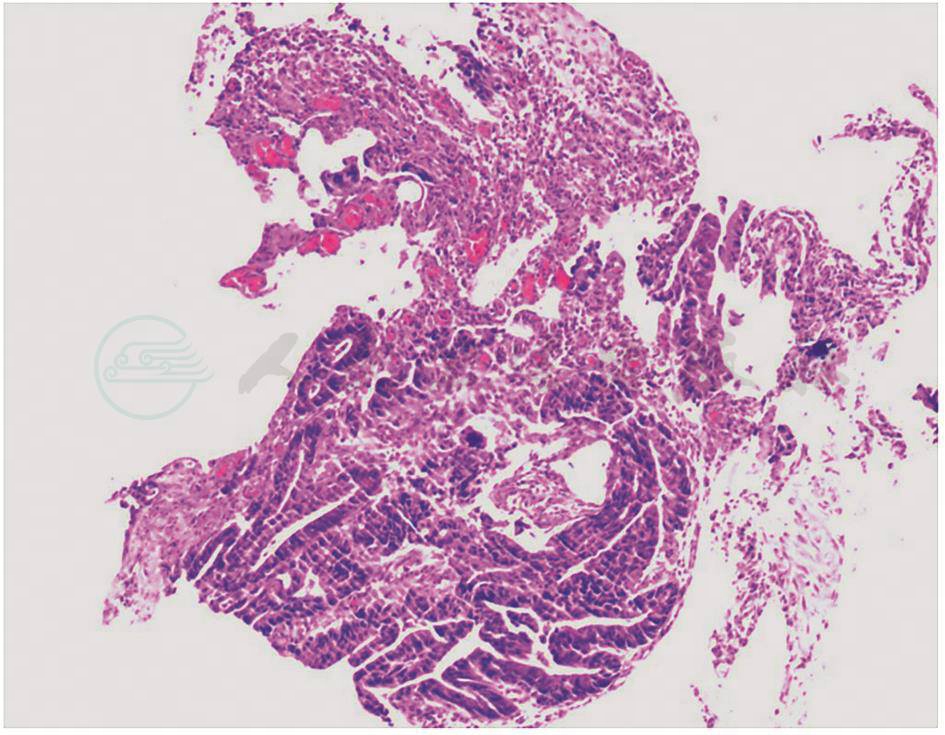

2020-03-30:行腹腔镜辅助胰十二指肠切除术(改良Blumgart胰肠吻合),术中见腹腔内无明显转移结节,胰头-十二指肠周围水肿呈硬块状,范围约8cm×8cm(图9)。切除标本后,可见:壶腹部有一1.5cm×1.5cm大小肿物,侵及胰腺及十二指肠,胆管及胰管内可见陈旧性积血(图10)。术中冰冻结果:胰腺中-低分化腺癌。常规病理结果:“壶腹部”胰胆管型中低分化腺癌,大小1.5cm×1.5cm,侵及十二指肠黏膜下层、胰腺实质(图11)。神经、脉管累犯阳性,周围组织见大片液化坏死伴肉芽组织增生。淋巴结2/18。pTNM分期T3aN1M0。免疫组化:CK7(-)、CK20(-)、CDX2(弱+)、P53(突变型)、Ki-67(约30%)。

图11 常规病理图片(HE染色,20×)